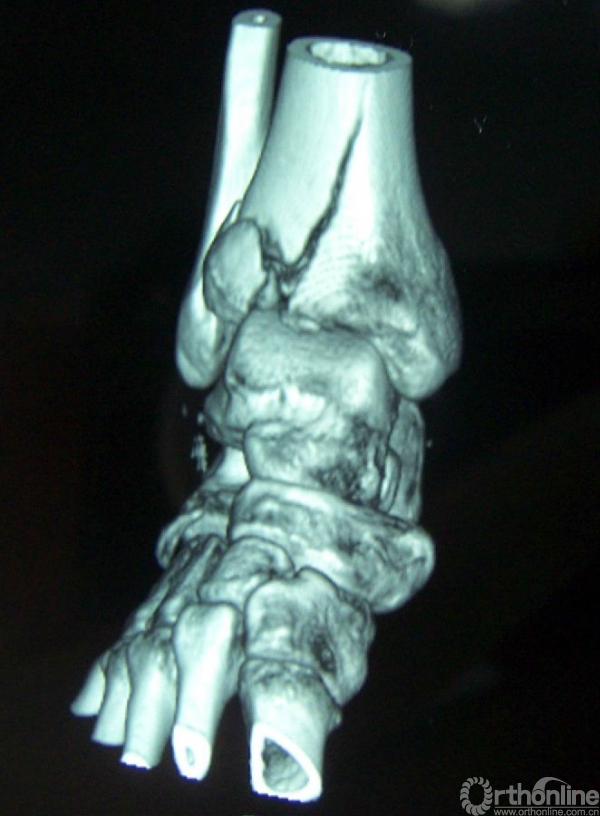

4b.CT水平面扫面及表面重建示内侧柱及中柱有明显的骨折;

4b